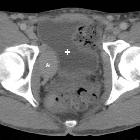

Post-thrombotic

aneurysmal dilatation of the hypogastric vein. The venous phase acquisition (d-h) showed the lesion (*) to enhance homogeneously and synchronously with venous vessels, consistent with aneurysmal dilatation of the proximal hypogastric vein. Urinary bladder (+).

aneurysmal dilatation of the hypogastric vein. Coronal (f) and sagittal (g,h) reconstructions confirmed aneurysmal dilatation (*) of the right hypogastric vein without signs of thrombosis. No abnormal dilatation, compression or thrombosis of the inferior cava, common and external iliac veins.